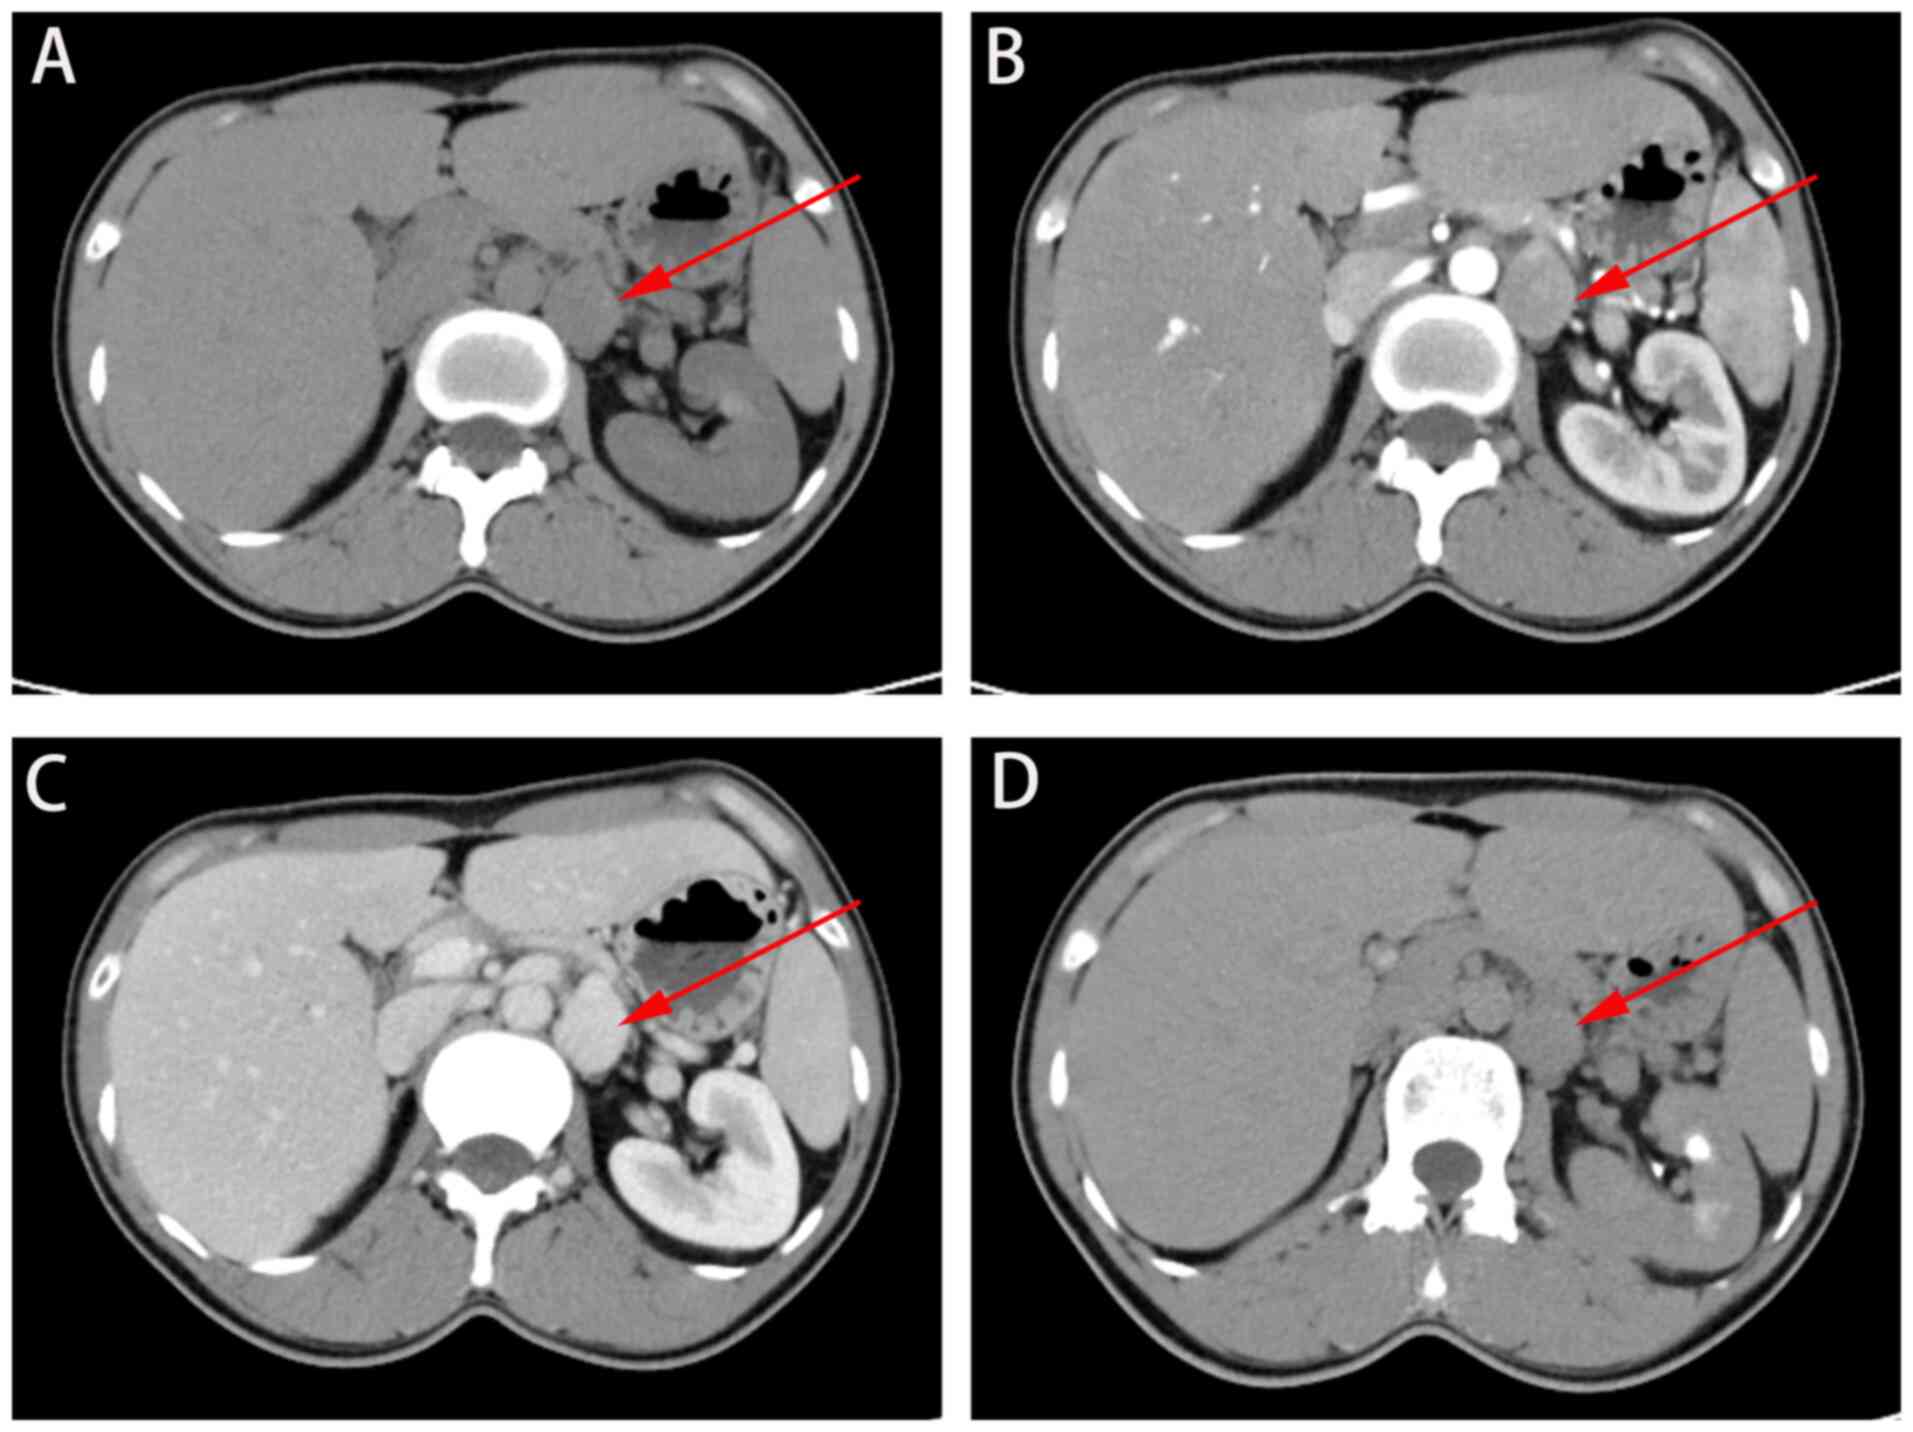

The present study reports on a 37-year-old man with a left renal venous hemangioma. The patient presented with frequent urination for 1 week, urgency for 1 week, urethral pain for 1 week and hematuria for 1 day at Zhangye People's Hospital affiliated with Hexi University (Zhangye, China). Physical examination revealed no palpable lumps, vertebral tenderness or skin damage. Upon admission, blood examination revealed normal levels of white blood cells, red blood cells, platelets and coagulation. CT revealed a left retroperitoneal mass, considered a left adrenal tumor (Fig. 1). Surgical treatment was performed, and a 3x2.6 cm, dark-purple soft mass was found next to the left renal vein, which was compressed and deformed (Fig. 2A). A left renal venous hemangioma was suspected (Fig. 2). Left renal venous hemangioma resection was performed, resulting in the disappearance of the patient's hematuria symptoms postoperatively. Pathological examination revealed a gray-red mass with smooth wall and visible smooth muscle on hematoxylin-eosin staining; combined with clinical findings, this confirmed the presence of a left renal venous hemangioma (Fig. 3). The patient was satisfied with the treatment and recovered well before being discharged.

Figure 1

Left retroperitoneal mass. (A) Computed tomography plain scan, (B) cortical phase, (C) medullary phase and (D) excretory phase (red arrow).